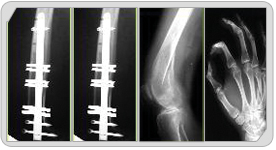

BioFix for bone fracture

Biofix using in Ti-Nickel shape memory

alloy has great potential as a fracture

fixation device in orthopeadic , Neurosurgical

and plastic surgery due to unique thermal

shape memory effects, superelasticity and

high damping properties.

TiNi shape memory bone stapler

(BRM-SH system) is more effective

and easy in application to some fractures

than cerclage.

This double ring might be more effective

and auxiliary to IM nail system in

spiral fracture to split fracture

occurred during hip stem insertion. |